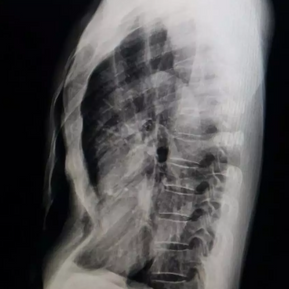

The anterior chest wall exhibits an obvious depression, causing severe compression and displacement of the heart to the left thoracic cavity. The Haller index is notably high at 5.6.

The patient is a 59-year-old male who has had a sunken chest since childhood, and the depression worsened gradually after adolescence. From the age of 30, he began experiencing chest tightness, which became more pronounced during vigorous activities. Three years ago, the patient underwent surgery to remove a cyst from his left lung, during which a rib from the left chest wall was removed, but no treatment was done for the pectus excavatum. Over the past two years, his symptoms have significantly worsened, leading to chest tightness, breathlessness, and difficulty breathing even at rest.